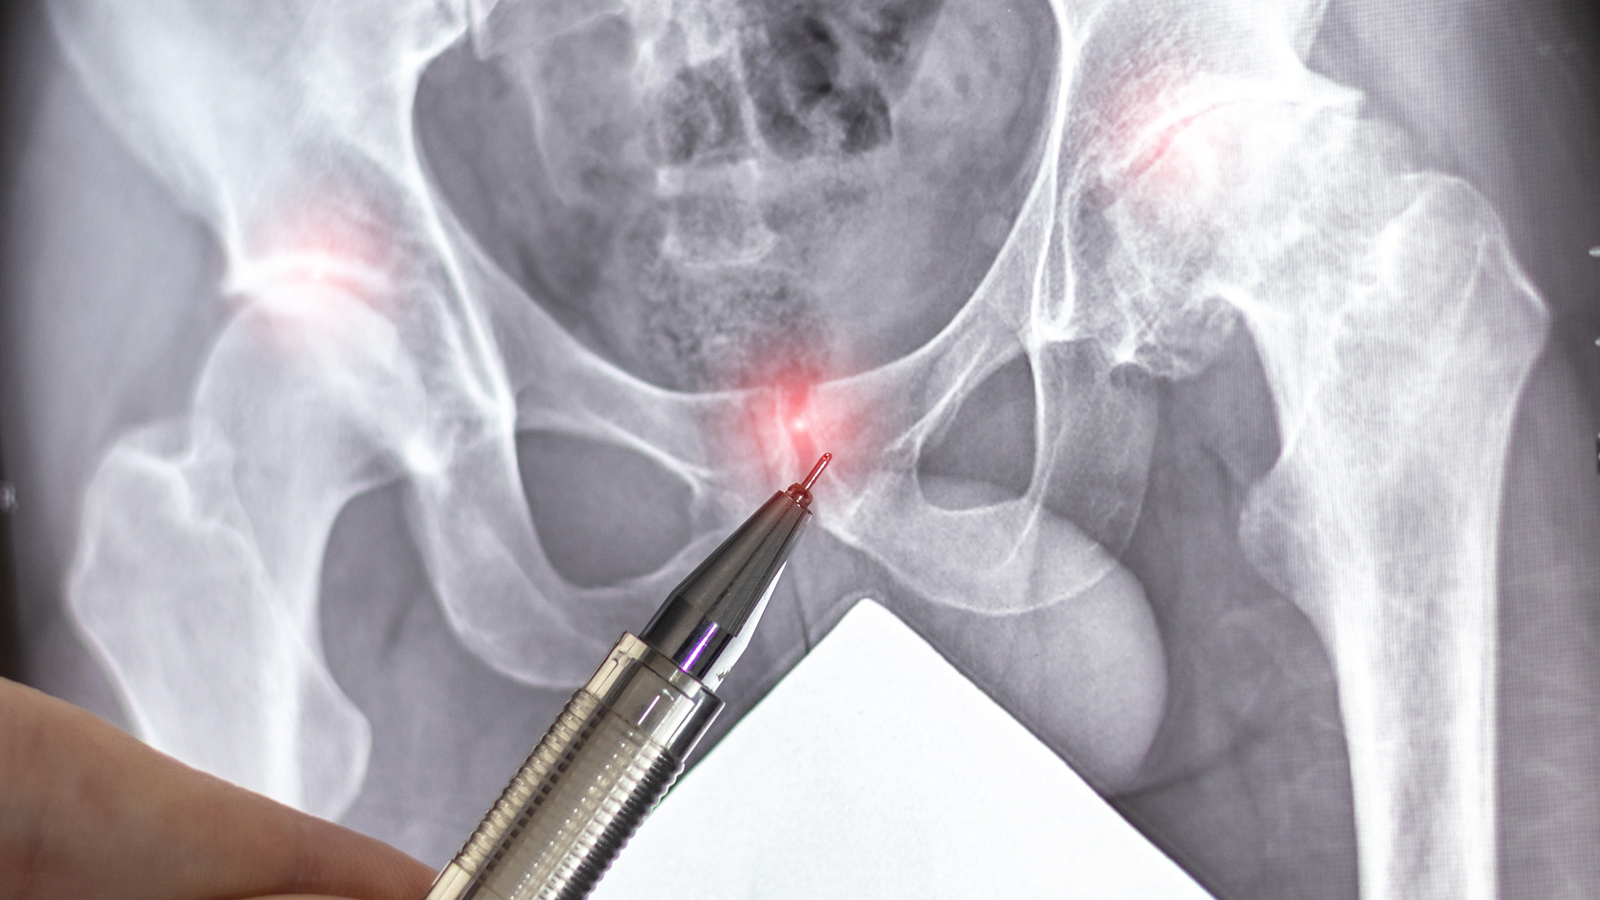

Being told that imaging has found a “multicystic pelvic mass” can be frightening. Many people immediately worry about ovarian cancer or a serious gynaecological condition—especially when scans show complex or multiloculated cysts.

However, not all complex pelvic cysts are ovarian tumours or malignancies. Some rare but benign conditions can closely mimic cancer on imaging, making diagnosis challenging even for experienced clinicians.

This article explains two such conditions—subserosal adenomyotic cysts and peritoneal inclusion cysts—and why awareness of these diagnoses matters. Drawing from published clinical cases in Singapore and broader specialist experience, it highlights how careful evaluation and specialist insight can help avoid unnecessary anxiety and intervention.

Why some pelvic cysts are misdiagnosed

Large, multiloculated pelvic cysts often raise concern because:

- They may appear complex on ultrasound or MRI

- They are sometimes separate from the ovaries

- Tumour markers may be inconclusive

As a result, these cysts are frequently misinterpreted as ovarian tumours or even malignancy, leading to anxiety and, in some cases, extensive surgery.

Two rare conditions that can present this way are adenomyotic cysts and peritoneal inclusion cysts.

How are these conditions diagnosed?

Unfortunately, imaging alone cannot always give a definitive diagnosis.

- Ultrasound and MRI are helpful for characterisation

- Tumour markers may be normal or mildly raised

- Final diagnosis often requires surgical assessment and histology

This is why these conditions are sometimes only diagnosed after surgery intended to rule out malignancy.